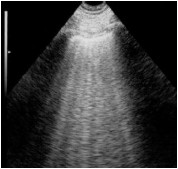

Paciente de 70 anos do sexo masculino dá entrada no Pronto-Socorro após iniciar quadro de dispneia em churrasco, há cerca de 1 hora.

Relata ser hipertenso e ter insuficiência cardíaca. Ao exame clínico, dispneico, FR 30, SatO2 77% em ar ambiente, FC 110 e PA 190x120, com ausculta pulmonar com estertores finos até ápices.

Assinale a opção que apresenta a imagem de ultrassonografia pulmonar compatível com a descrição do quadro acima.